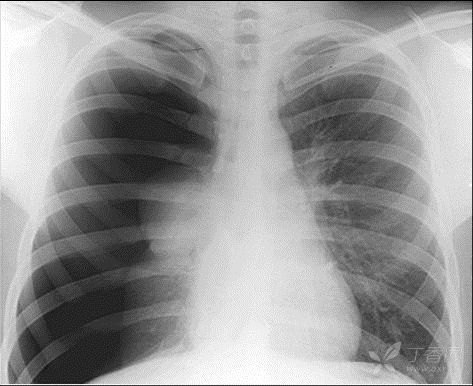

自發(fā)性氣胸的典型表現(xiàn)是突發(fā)的胸痛和氣短,可有咳嗽,癥狀的嚴(yán)重程度與氣胸的多少(胸膜腔內(nèi)氣體的多少,即氣體壓迫肺組織的程度)及與有無伴發(fā)的疾病有關(guān),例如患有嚴(yán)重肺氣腫的患者,呼吸功能也很差,即使較小范圍的氣胸,也可有明顯的癥狀,需要積極的處理。自發(fā)性氣胸的最重要的檢查手段是X線正、側(cè)位胸片,可判斷氣胸的范圍、程度和有無伴發(fā)疾病。

突然出現(xiàn)胸痛、呼吸困難應(yīng)立即到醫(yī)院做X線檢查,胸片上顯示無肺紋理的均勻透亮區(qū)的胸膜腔積氣帶,其內(nèi)側(cè)為弧形的線狀肺壓縮邊緣,可確診稱為氣胸。但有其他一些急癥也有類似表現(xiàn),如急性心肌梗塞、急性肺栓塞、肺大皰、急腹癥等,如果X線檢查未見氣胸征象,應(yīng)立即做進(jìn)一步檢查以明確病因,如心電圖等。